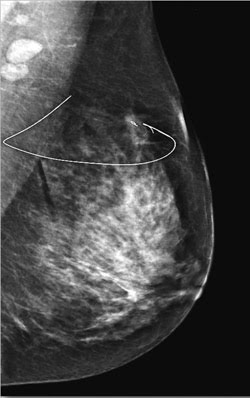

Physicians and other hospital and clinic end users are increasing their demand for optical sensors on the medical devices they already use every day. Improved imaging systems are being sought after, with speed and resolution the top drivers. The new technologies of note include positron emission mammography, OCT systems that operate at various infrared wavelengths, advanced picture archiving communications systems, breast-specific gamma imaging and the aforementioned photodynamic therapies.